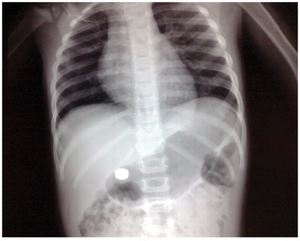

Button battery in stomach on KUB.

Button Battery

- Call the National Button Battery Ingestion Hotline: 202-625-3333 (24/7) [8]

- True emergency if located in esophagus

- Perforation can occur within 6hr of ingestion

- via direct pressure or electrical conduction leading to liquefactive necrosis

- Mercury toxicity

- Obtain urgent endoscopic removal

- Batteries past the esophagus can be managed expectantly with 24hr follow up